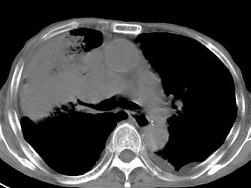

问题 男,68岁,胸闷,咳痰,咯血二月余,胸部CT如图,最可能的诊断为 ( )

选项 A、右上肺肉瘤 B、肺炎性假瘤 C、右肺中央型肺癌 D、右上肺炎 E、右上肺不张

答案 C